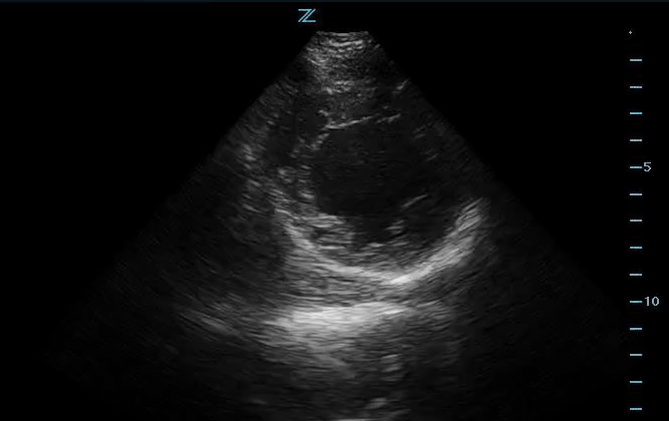

You do a bedside US shown below:

Parasternal long axis shows decreased EF as well as global hypokinesis.

To summarize the findings above, this patient has decreased ejection fraction with hypokinesis in the LV. Seven weeks post-partum, the raises concern of peri-partum cardiomyopathy.